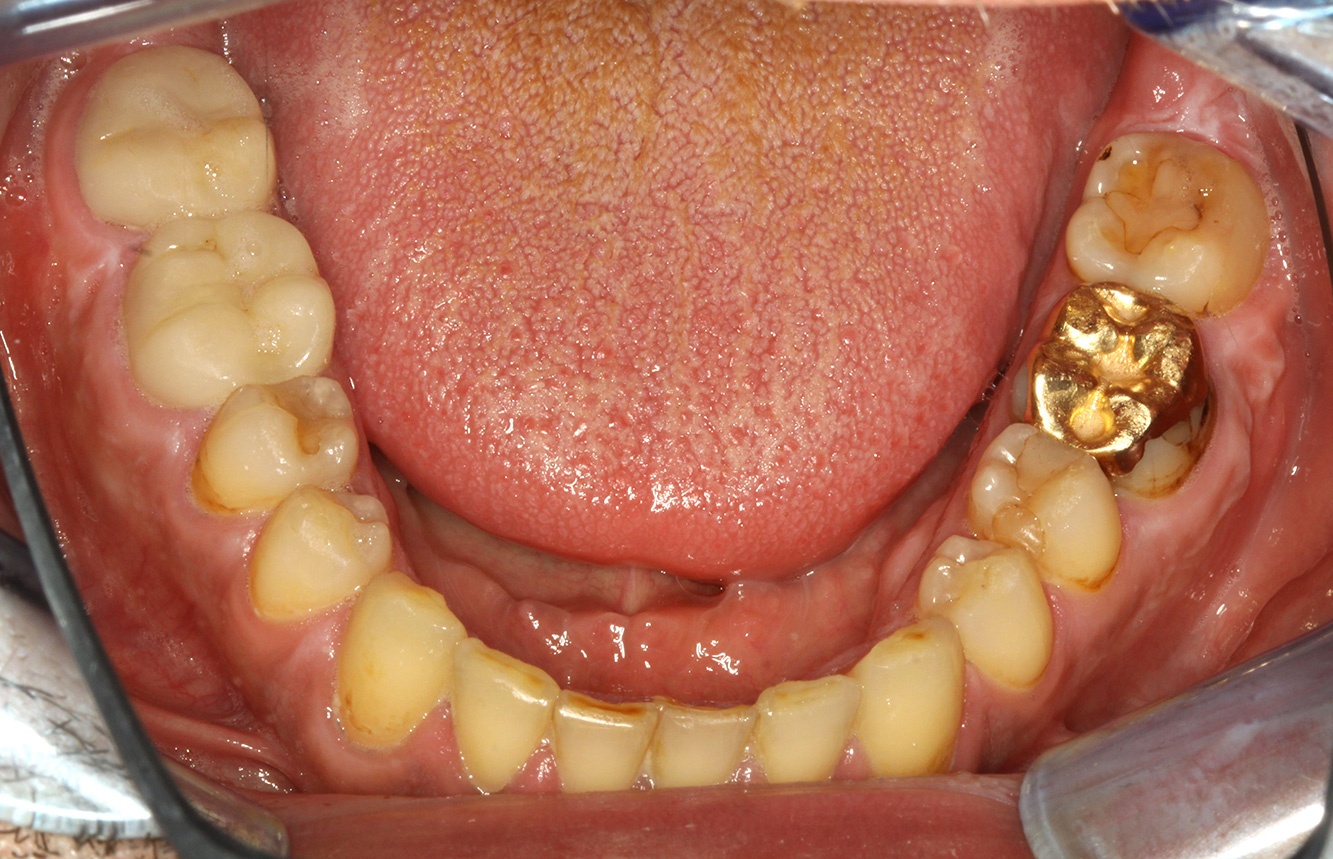

Pacient transplantat cu proliferări gingivale

Un pacient în vârstă de 71 de ani, cu transplant de rinichi și istoric de hipertonie (hipertensiune arterială) se prezintă în cabinet. Din cauza istoricului său medical, este necesară o medicație pe termen lung cu ciclosporină, pentru a suprima sistemul imunitar, precum și amlodipină pentru a reduce tensiunea arterială. Pacientul raportează, de asemenea, gingii sensibile și sângerânde. Din punct de vedere al sănătății orale, pacientul are lucrări dentare, o edentație de opt dinți, creștere gingivală pronunțată și parodontoză de gradul B, stadiul II, cu pungi active și carii radiculare inițiale la dintele 22. Evaluarea riscului de carie determină un risc moderat de carie (API 60). Se pot stabili următoarele recomandări de tratament pentru ședința de profilaxie. mai multe